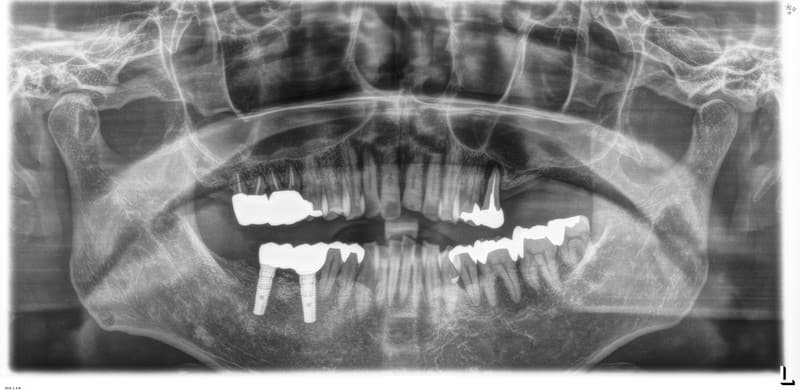

病歴や健康状態に関する問診、口の中の検査、レントゲン写真や歯型の採取